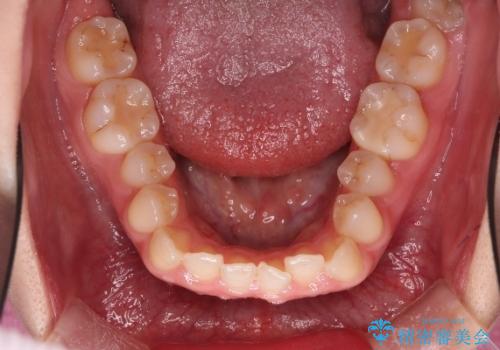

【オープンバイト】前歯のがたがたをなおしたい。

- 笑った時の前歯の見た目が気になることを主訴に来院されました。

上の歯が下の前歯を少し隠すぐらいを目指し、インビザラインにて治療を行いました。

オープンバイトの後戻りを防ぐためには舌のトレーニングが必要です。